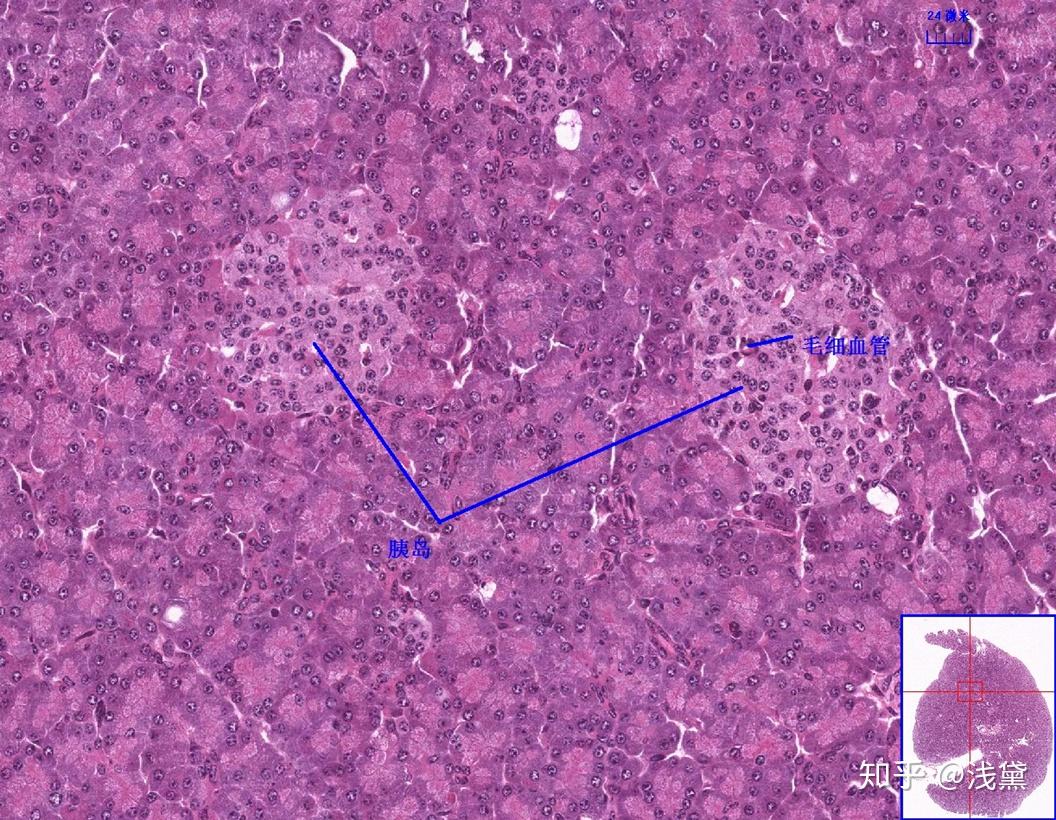

赫令体 垂体细胞 脑垂体的神经部